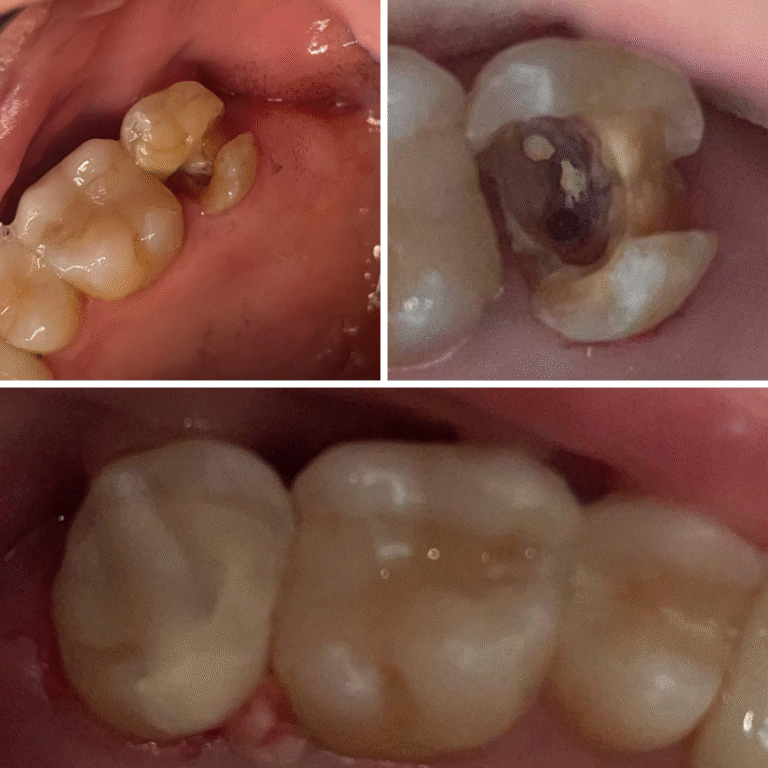

…aqueles tratamentos extensos que tem tudo para dar errado com resina indireta, mas tem remanescente suficiente que contraindica uma coroa de porcelana.

O Método de Esferas foi criado justamente para resolver essas dificuldades.

Um método simples, didático, reproduzível para todos os dentes posteriores e para os mais diversos casos de destruições , extensas ou não, dentes com retentores ou não!

🔹 Uma técnica de resina indireta validada clinicamente, com alto índice de sucesso

🔹 Controle anatômico, oclusal e estético com previsibilidade

🔸 Como realizar a técnica completa de resina indireta em dentes posteriores, do preparo à cimentação final.

Como confeccionar e adaptar resinas indiretas com precisão e naturalidade.

Estratégias de polimento e acabamento para resultados duradouros.

Controle de contatos proximais e prevenção de recidivas.

Sequência completa de cimentação e ajuste oclusal.